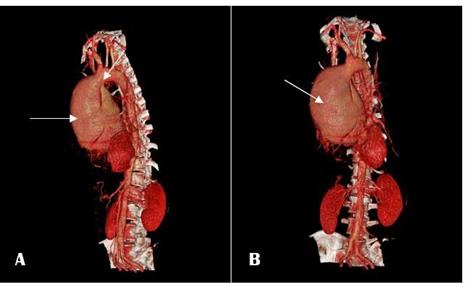

Aortografía (Imagen 3 y 4).

IMAGEN

4. Aortografia por TC reconstrucción en 3 dimensiones fase arterial: Aneurisma

sacular disecante de aorta ascendente

y parte de aorta descendente Tipo A de Stanford. Imagen A reconstrucción imagen anterior, Imagen B reconstrucción imagen posterior.

Fuente. Base de datos de la investigación. Elaborado por. Autores.